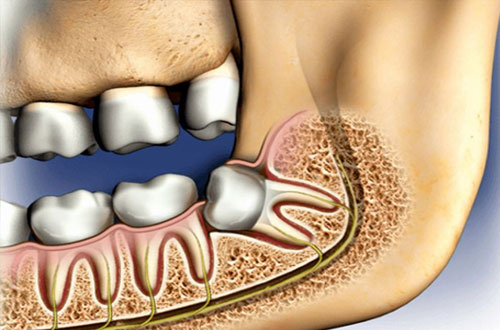

Ibland kan en operation av visdomstanden krävas och det kan då bero på att omständigheterna kring tanden gör så att den inte går att dra ut. Det kan exempelvis bero på att tanden har vuxit snett, drabbats av en omfattande infektion eller är retinerad, att tanden ligger kvar i käken täck av slemhinna och ibland även ben. Tandens rötter kan även vara böjda vilket gör att det är svårt att dra ut den. I de fall man måste ta bort en visdomstand som sitter komplicerat är operation det bästa alternativet.